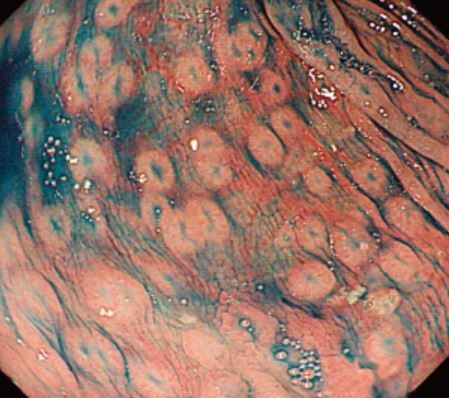

「多発性リンパ濾胞」あるいは「Cowden病」と誤診される危険のあるMLP(Multiple lymphomatous polyposis)型 濾胞性リンパ腫

神奈川医療センター板井先生の論文より引用させていただきました。

同症例の十二指腸 MLP(Multiple lymphomatous polyposis)では、十二指腸に特徴的な「白色隆起の多発」が見られるが、本症例でも見られています。